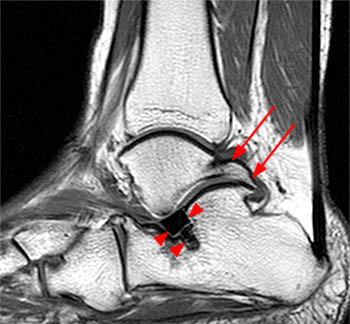

| Sag T1-weighted sequence demonstrates a prominent Stieda's process (asterisk) (which showed mild edema on a T2-weighted sequence) and a small dorsal tibial osteophyte (arrow). |